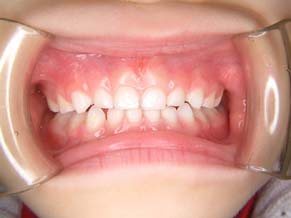

2か月後です。反対咬合は治っています。現在は正常な噛み合せになりました。

これからまだ永久歯に生え替わるので、注意深く定期的に観察していきます。生え替わった後に、また反対咬合になりこともあります。